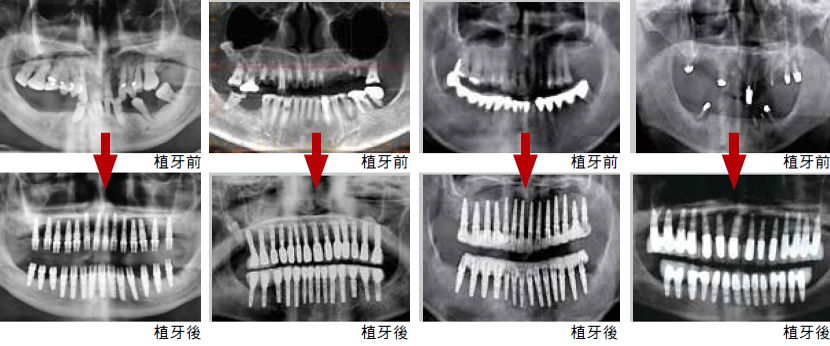

當天全口微創五合一即拔即植案例